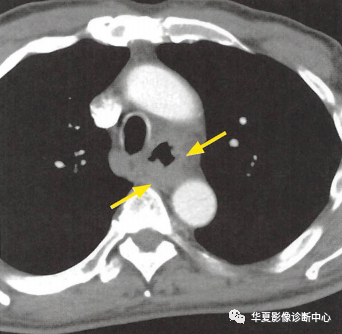

(上圖:增強CT食管壁不規則增厚)

①食管壁改變:食管壁全周環形或局部不規則增厚,相應平面管腔變窄或消失,呈腫塊樣改變;

②食管周圍脂肪間隙模糊、消失:提示食管癌向外侵犯;

③周圍組織器官受累:多為氣管和支氣管,常形成食管-氣管瘺,其次可侵犯心包膜、左心房和主動脈等;

④轉移:以縱隔、肺門及頸部淋巴結轉移多見,也可逆行性轉移至上腹部淋巴結,少見肺轉移。CT增強掃描可見瘤體輕度強化。較大瘤體呈不均勻強化,常合并低密度的壞死灶,較小瘤體強化均勻。